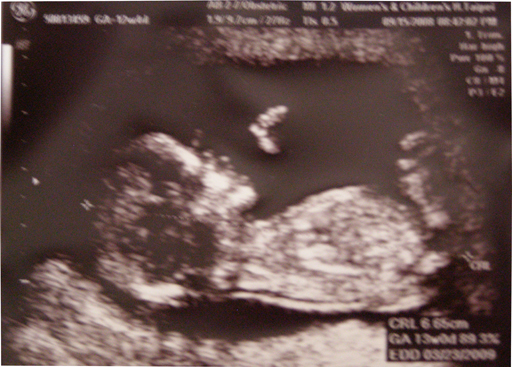

六點半時間一到,巴巴就說他已經先出門瞜,不過笨巴巴查到的婦幼是舊地址,為娘的我只好請他用導航順利來會合,而且我坐捷運時,在超級擁擠的人群中還有人讓位給我ㄟ,果然肚子明顯一點是有好處的:D,到醫院剛好7:30,但是婦幼還是讓我們等了一小時再進去照超音波,蕭醫師果然如網路傳言,放著古典音樂、夾雜的台語輕鬆地幫我們做檢查。這次照的很仔細,不過小牛超愛翻滾,一直沒法讓蕭醫師照到重要角度,蕭醫師說他照了12小時,小牛是最皮的一個,翻個不停,我跟巴巴一直笑個不停,因為小牛的動作真的很好笑,而且他不再是小叮噹手瞜,已經有手指、腳趾,還會握手、翹腳哩,身體也長到6.5cm瞜!

檢查30分鐘後,宣布答案唐氏症機率是1/16648非常正常,而且預產期跟黎醫生說的一樣,都是在3/26(正好是我們結婚三周年說)不過媽媽有項血液檢查值偏低,未來可能會有生長遲滯的狀況,所以媽媽還是要很小心,希望小牛多合作,吃多點、吸收好一點,別讓媽媽擔心耶!